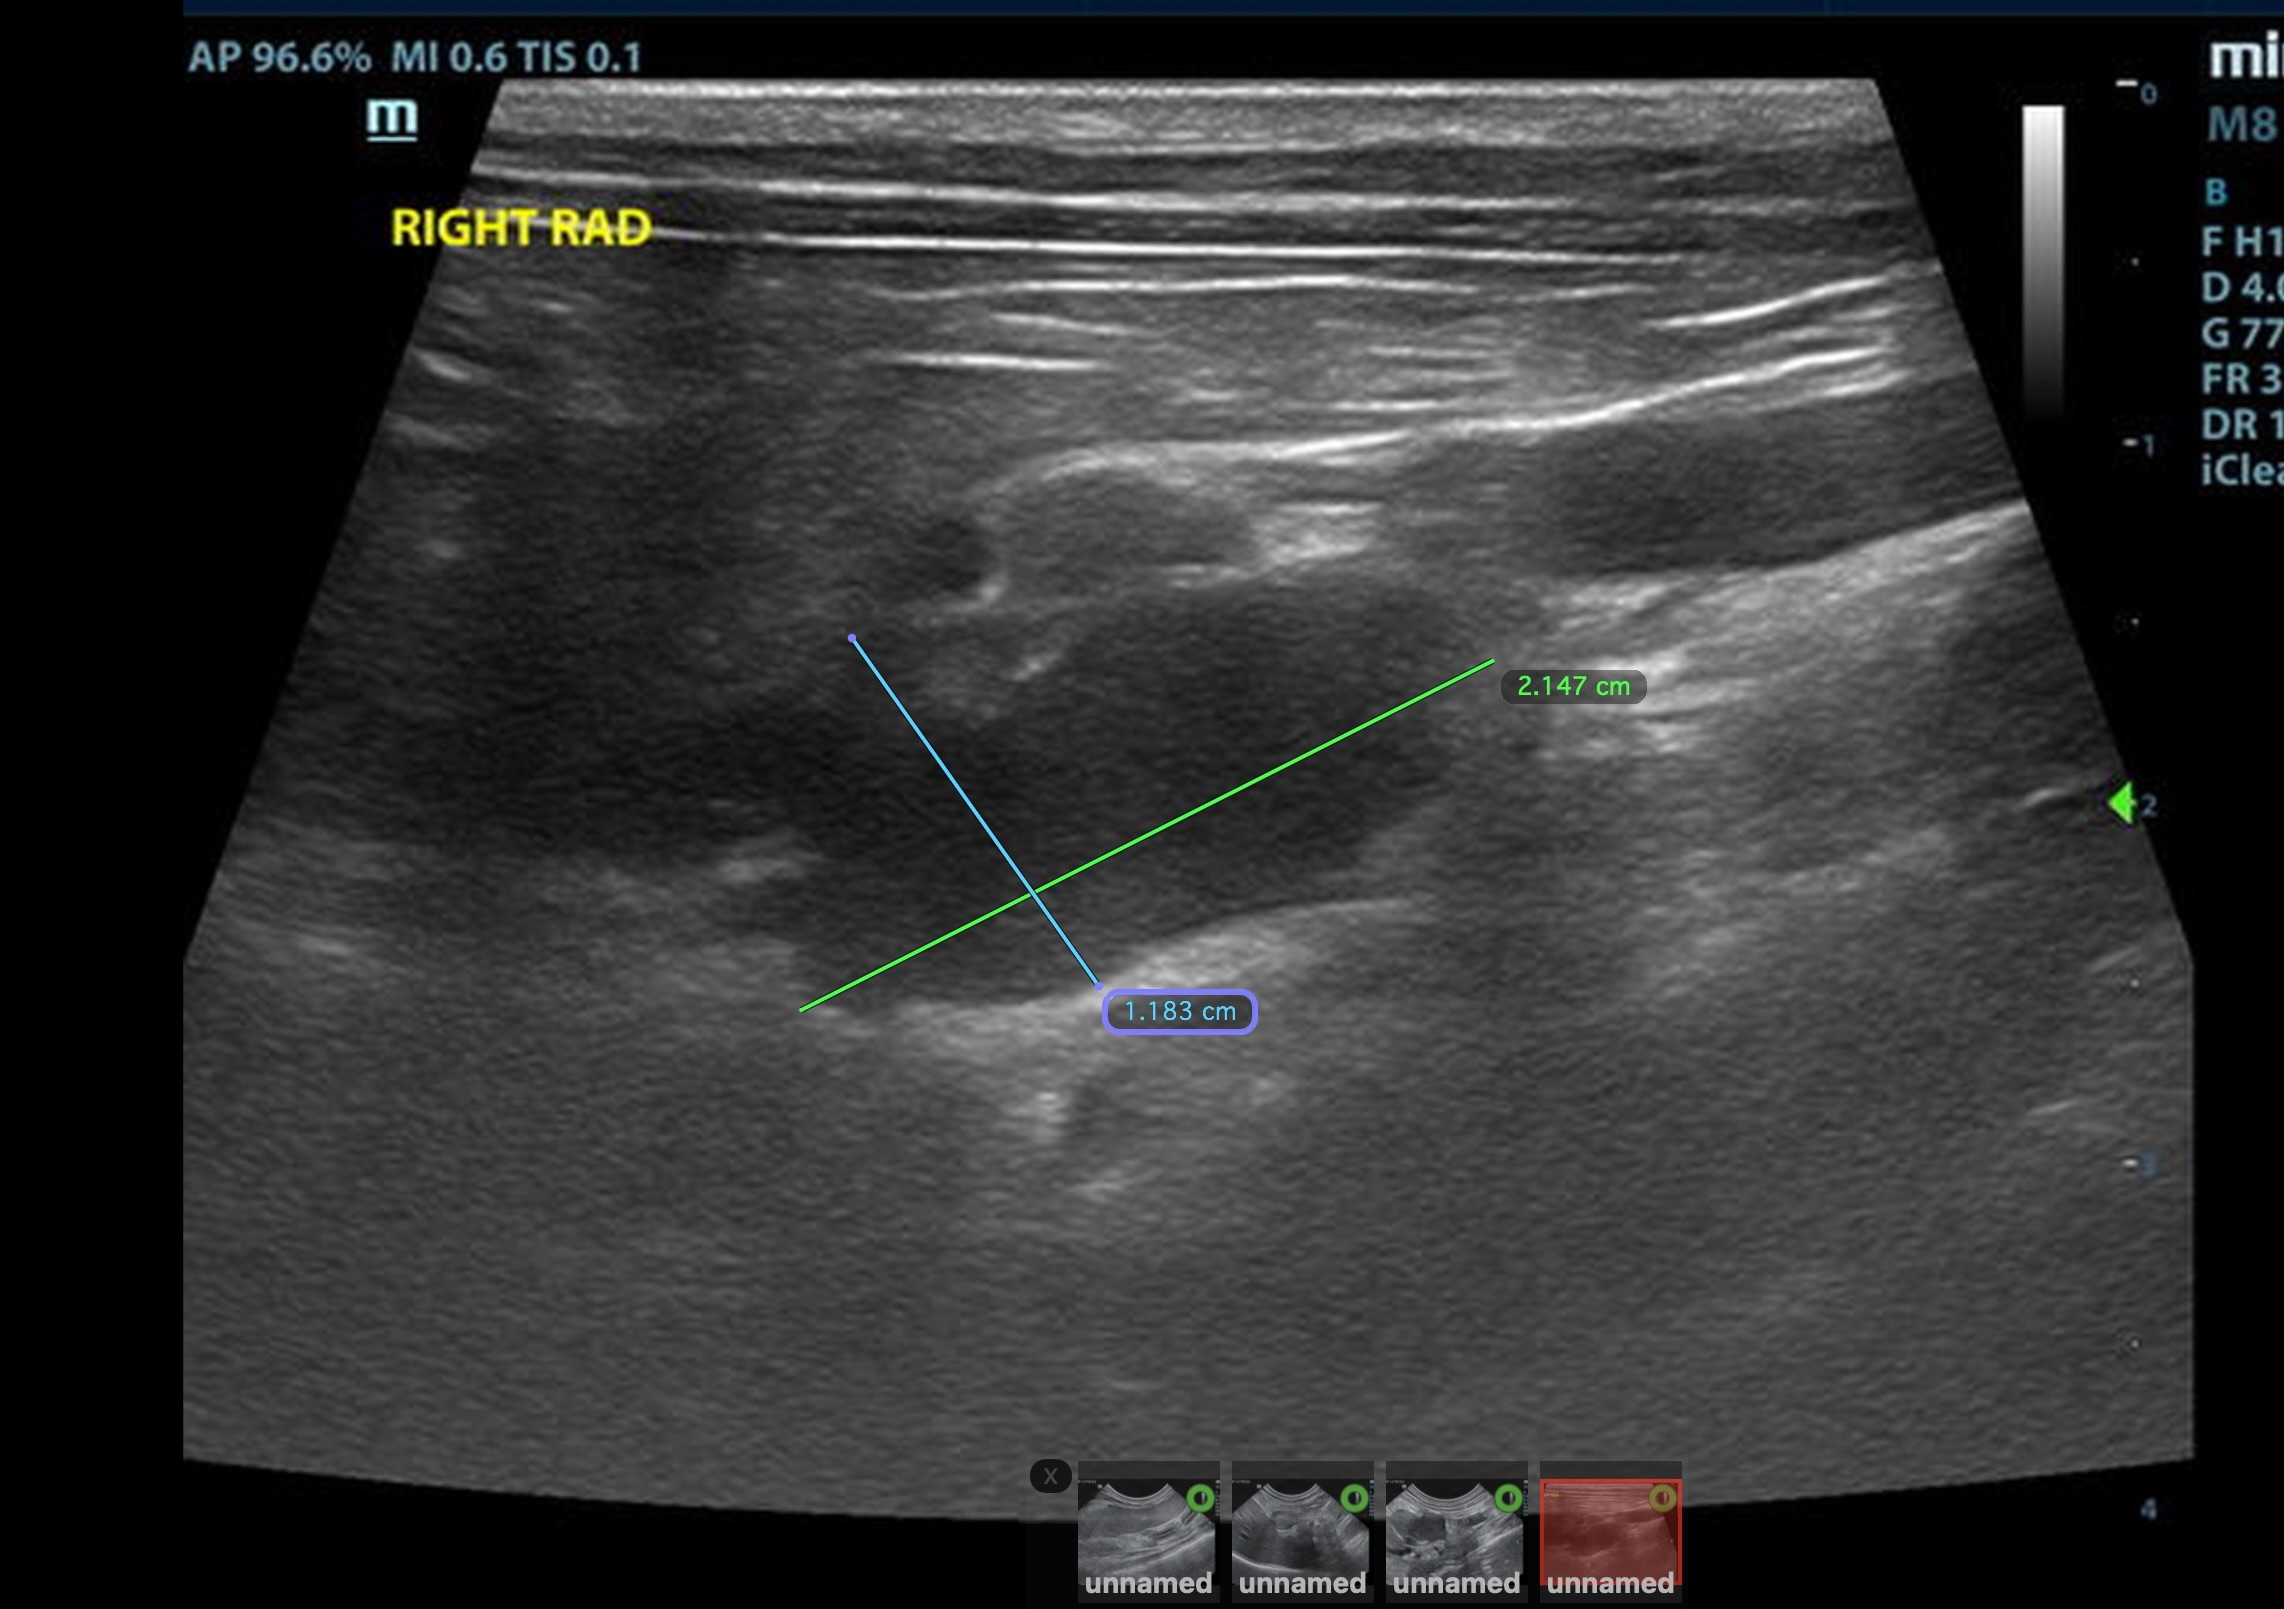

The left adrenal gland was visualized and recognized as normal for this breed. The left adrenal gland measured 0.7 c 0.35 cm. The region of the right adrenal gland revealed a mineralizing mass that impinged upon the vena cava and appeared to be occupying the phrenic vein; it measured 2.2 x 1.2 cm. This appears to be isolated. Normal right adrenal gland was not found.

right kidney to right likely right adrenal mass

Right kidney to likely right adrenal mass. Note the norma left adrenal at the end of the video loop